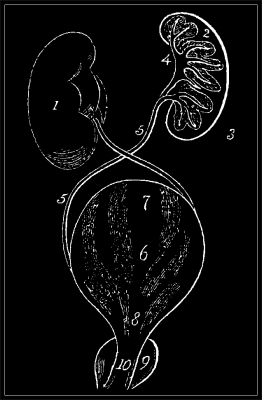

The Urethra, or water passage, is the canal that passes through the spongy body to the bladder. The urine and[11] semen pass through it. It is very elastic, and may be dilated so as to admit a large instrument to be passed into the bladder, and it contracts on the smallest. It is supported in its course by the spongy body and the prostate gland, between which is a portion unprotected, called the membranous portion. The passage varies in its size in different parts: thus it is rather contracted at the orifice, enlarges within, and for an inch again contracts, dilates nearer the bulb, diminishes at the membranous portion and near the prostate gland, and finally enlarges into the bladder. The cut opposite will show these parts.

a. Bladder, or receptacle of urine.

b. Ureters, or passages through which the urine comes from the kidneys, where it is formed, to the bladder.

c. Vas Deferens, through which the semen passes from the testicle, where it is formed, to the seminal vesicles, where it is matured.

d, d. Openings of Ureters into the bladder.

e. Prostate Gland.

f. Orifices of excretory ducts.

g. Openings of the seminal ducts.

h. Ischio-cavernous muscles.

i. Bulb of Urethra divided.

k. Cowpers Glands.

l. Wide part of Urethra.

m. Narrow part.

n. Fossa Navicularis, usually affected in gonorrhœa.

o, p. Prepuce.

k. Cowper’s Glands.

The bladder is the reservoir of the urine, which is formed in the kidneys, comes into the ureters, passages leading from the kidneys to the bladder, and thence flows, drop by drop, into the bladder. The bladder is shaped somewhat like a pear, but this shape is varied by its contents, and the relative condition of its adjacent parts. Thus, when the bladder is full, its upper part may be felt rising above the pubis, that portion of the lower part of the belly that is covered with hair. In very fat persons the bladder is flattened by the weight of the intestines, and obliged to find room where it can, as in pregnant women. Anatomists, when describing the bladder, speak of its body, base, or upper part, sides and neck, where the urethra or water passage begins, and which is surrounded by the prostate gland. These parts are seen in the first engraving on the opposite page.